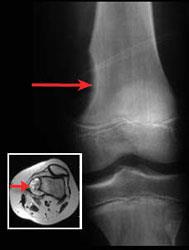

How Bone Cancer Is Diagnosed

A bone scan may be used to help determine the stage of a bone sarcoma. Types of biopsy procedures used to diagnose bone cancer include: The amount of radiation in the.

Symptoms such as bone pain or swelling often prompt a visit to a doctor. (for more on this, see signs and symptoms of bone cancer.) for people at higher risk. A bone scan is a nuclear medicine test.